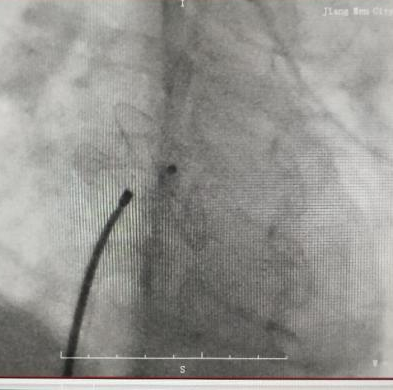

(4)心血管亚专科:收治小儿心肌炎、心力衰竭、心律失常、先天性心脏病、后天性心脏病包括川崎病冠脉病变等多种儿科心血管疾病,为江门地区唯一开展儿童先天性心脏病微创介入手术单位,目前已完成一百多例,效果良好。